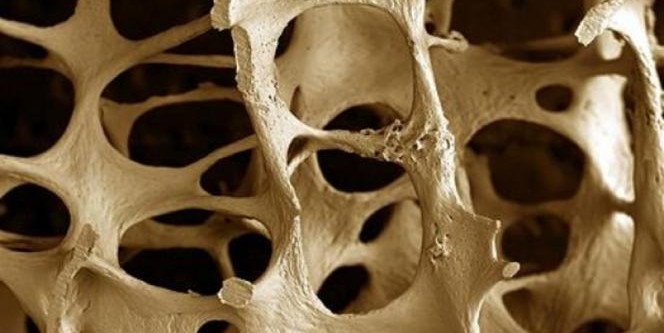

La osteoporosi è una malattia legata all’invecchiamento che colpisce una donna su quattro dopo i 65 anni. Per chi soffre di questa patologia, le ossa diventano molto più fragili, e bastano anche solo dei colpi di tosse o scontrarsi con qualcosa per fratturarsi le ossa, spesso l’anca, le braccia, il polso e la schiena. Lesioni da cui spesso è difficile riprendersi completamente.